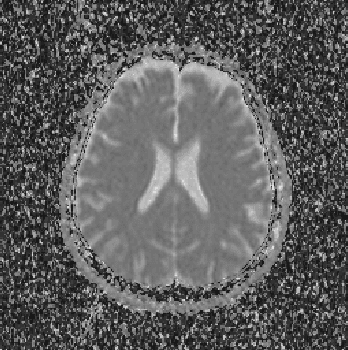

Abstract:The materialist dialectical method is a philosophical investigative method to analyze aspects of reality. These aspects are viewed as complex processes composed by basic units named poles, which interact with each other. Dialectics has experienced considerable progress in the 19th century, with Hegel's dialectics and, in the 20th century, with the works of Marx, Engels, and Gramsci, in Philosophy and Economics. The movement of poles through their contradictions is viewed as a dynamic process with intertwined phases of evolution and revolutionary crisis. In order to build a computational process based on dialectics, the interaction between poles can be modeled using fuzzy membership functions. Based on this assumption, we introduce the Objective Dialectical Classifier (ODC), a non-supervised map for classification based on materialist dialectics and designed as an extension of fuzzy c-means classifier. As a case study, we used ODC to classify 181 magnetic resonance synthetic multispectral images composed by proton density, $T_1$- and $T_2$-weighted synthetic brain images. Comparing ODC to k-means, fuzzy c-means, and Kohonen's self-organized maps, concerning with image fidelity indexes as estimatives of quantization distortion, we proved that ODC can reach almost the same quantization performance as optimal non-supervised classifiers like Kohonen's self-organized maps.